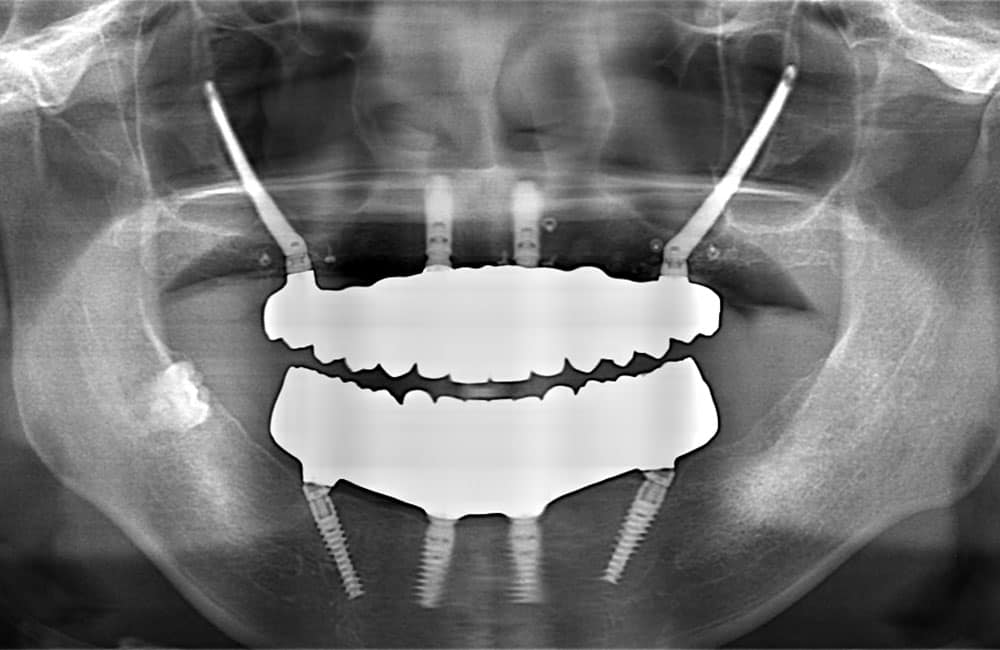

01All-on-4 Hybrid

前方は通常のインプラント、後方にザイゴマインプラントを用い上部構造を支える方法を、一般的にオールオンフォーハイブリッドと呼びます。

症例

02All-on-4 Hybrid+2

噛む力が強い場合や、上下顎の噛み合わせの関係を考慮し、前方に4本のインプラントを入れ、後方にザイゴマインプラントを用い上部構造を支える場合があります。一般的にオールオンフォーハイブリッドプラスツーと呼びます。